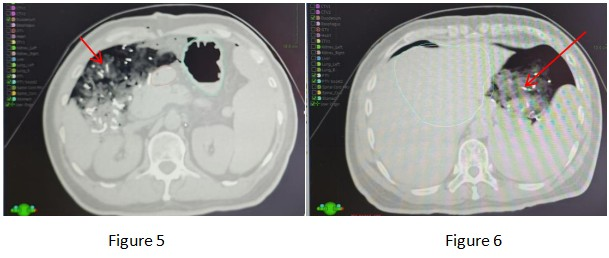

After multidisciplinary consultation in our hospital and with the patient being fully informed and giving consent, we performed a technique pioneered in our hospital, namely exploratory laparotomy + placement of gauze pads to isolate the uninvolved organs (the red arrows in the figure all point to the imaging of the gauze pads).

Among them, multiple departments such as the Department of Surgery, the Department of Anesthesiology, the ICU, the Radiotherapy Physics Room, the Radiotherapy Technology Room, the Imaging Department, the Carbon Ion Operation and Maintenance Personnel, and the Ambulance Transfer Staff actively cooperated. After the surgeon evaluated the patient's surgical conditions, an exploratory laparotomy + placement of gauze pads to isolate the stomach and duodenum was performed under general anesthesia. A total of 15 pieces of gauze and one gauze strip were used. The intraoperative bleeding volume was approximately 20 ml, and the operation time was 40 minutes.

After the verification was passed and the errors were eliminated, the patient received a single high-dose radical radiotherapy. The intraoperative radiotherapy dose was 20 Gy (RBE)/1Fx.